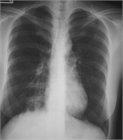

1. Q熱コクシエラ肺炎症例の胸部X線所見は典型例では多発性の肺野斑状影を呈する。